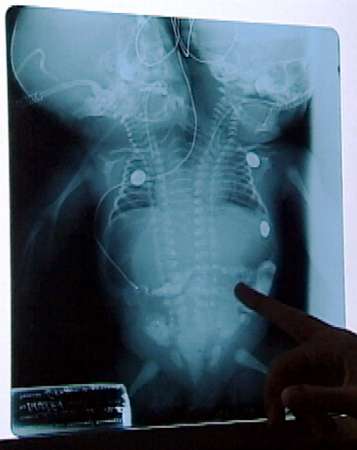

Menina de duas cabeças pode morrer a qualquer momento

A menina de apenas cinco dias de vida, que você vê na foto ao

lado, nasceu com duas cabeças.

Ela ainda não tem sequer nome, mas foi desenganada nesta

quarta-feira pelos médicos do Hospital Roosevelt, da Guatemala.

Eles dizem que não podem fazer nada porque apesar das duas

cabeças, a criança tem apenas um coração. A menina teria também somente dois

braços e duas pernas.

A mãe da criança siamesa, com poucas chances de vida, é uma

menina de apenas 15 anos.

Segundo os médicos, o caso é raro e só aparece um em cada

900.000 nascimentos.